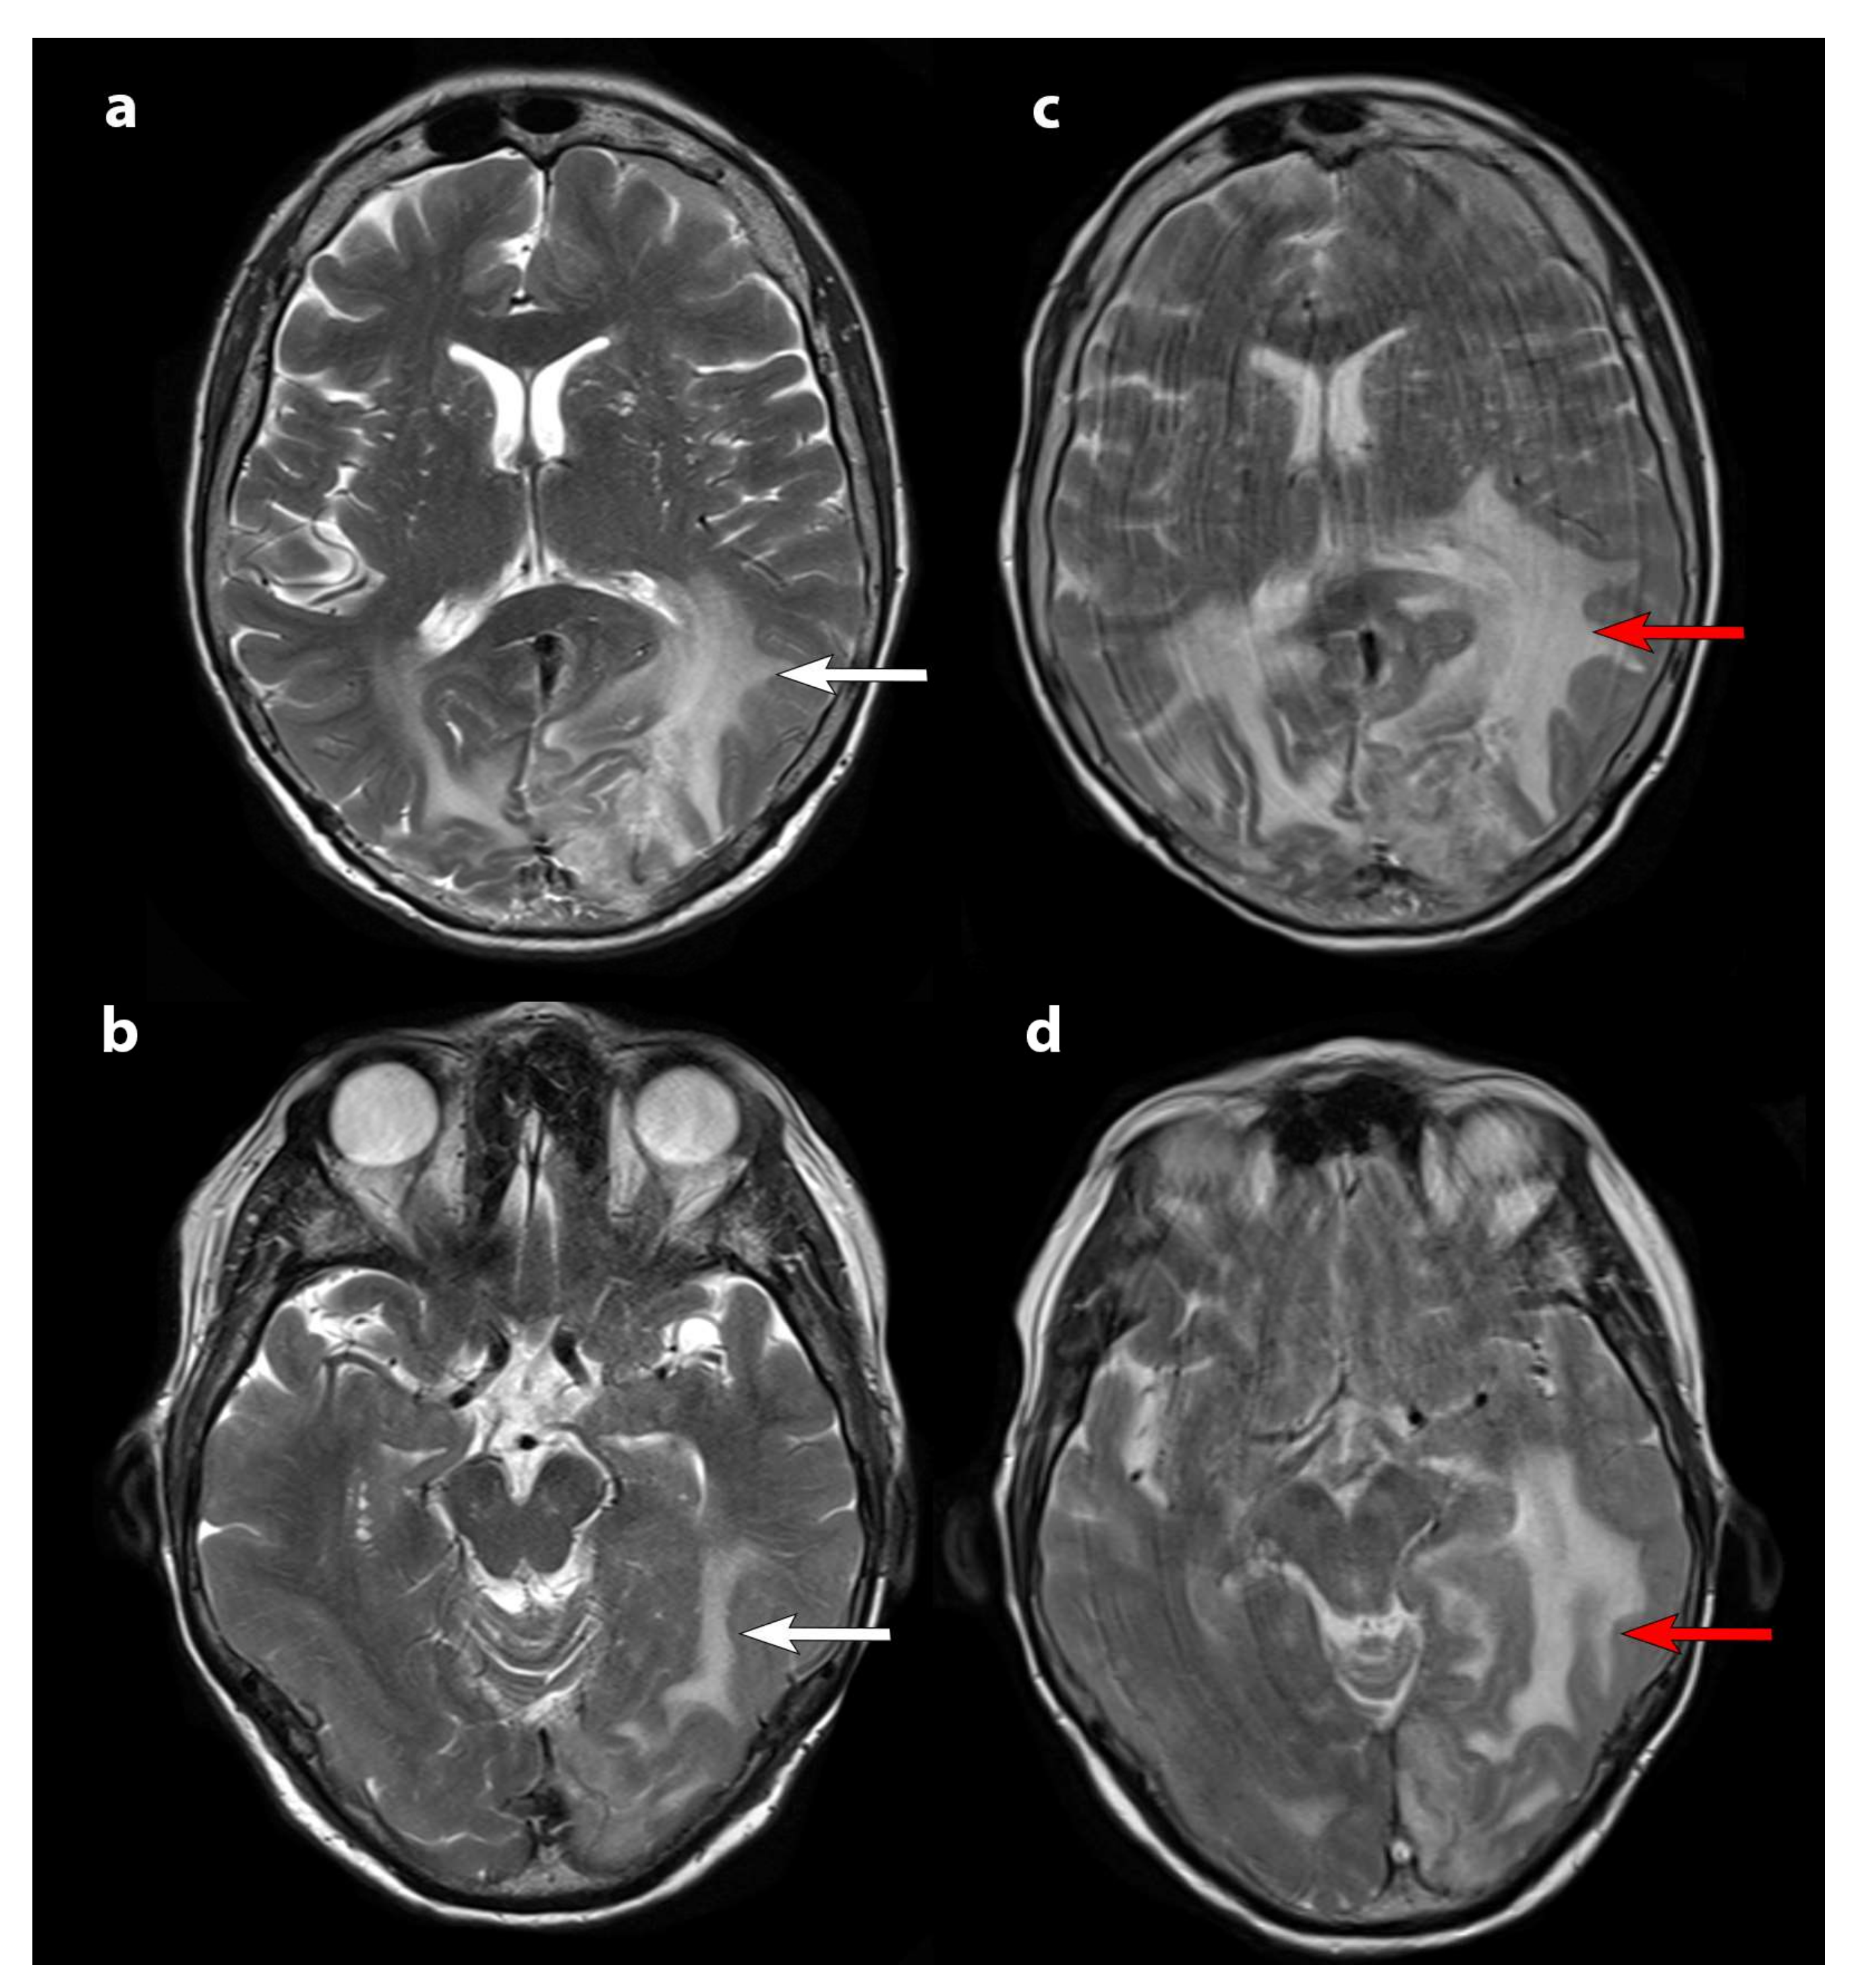

2.2. Imaging

2.4. MRI Response Assessment